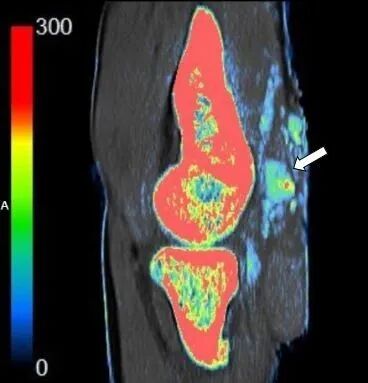

与X线平片及单能量CT相比,双能量能谱CT能够超早期显示更细小的尿酸盐结晶的存在;与MRI相比,双能量能谱CT可以进行多关节的扫描成像,不仅能够直观分析检查部位是否有尿酸盐结晶存在, 并且可以分析其数量、大小、形态、位置、分布以及临近关节骨质及软组织损害的情况。

腕关节尿酸盐(痛风石)沉积